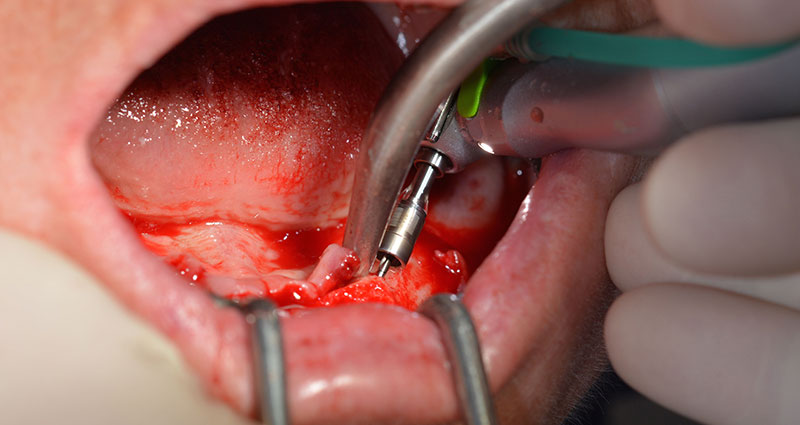

Prima di tutto, è stato individuato il forame mentoniero come limite della struttura anatomica. Successivamente, l'osso corticale della cresta è stato lisciato con un manipolo e una fresa larga a rosetta (Fig. 4).

A questo punto si possono già intuire i vantaggi che garantisce Implantmed. Il protocollo chirurgico è già predefinito e gli strumenti sono collocati in posizione fissa. Le posizioni individuali possono essere selezionate premendo la lettera "P" con il controllo a pedale o tramite il display. La velocità predefinita è di 35.000 giri/min nella posizione 1 e, in questo caso, i numeri sono visualizzati sul display illuminato (Fig. 5 e 6).